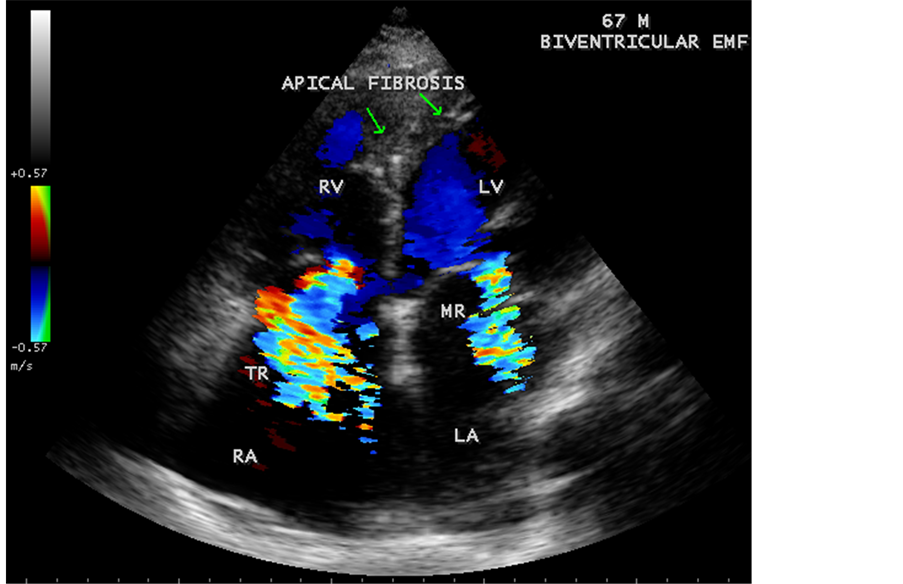

Figure 34. Biventricular EMF showing AV (atrioventricular) valve regurgitation in a 67-year-old male.